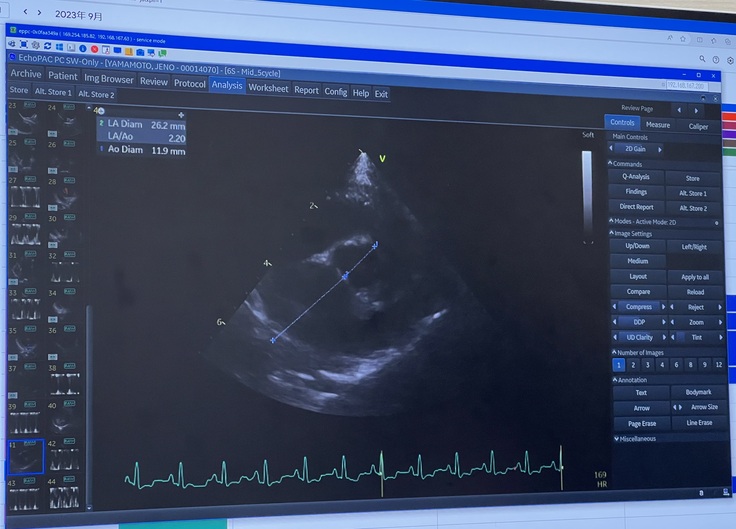

検査の結果は、

初めての「良くなっている」というお言葉をいただきました😭

前回、薬を増やしたおかげで、肥大していた心臓が少し小さくなってくれていました。

そのおかげで弁と言われる血液が一方通行に流れる為のフタのような役割のものが近づいて、逆流を少し防いでくれてるとの事でした。

(※心臓の検査 エコー写真)